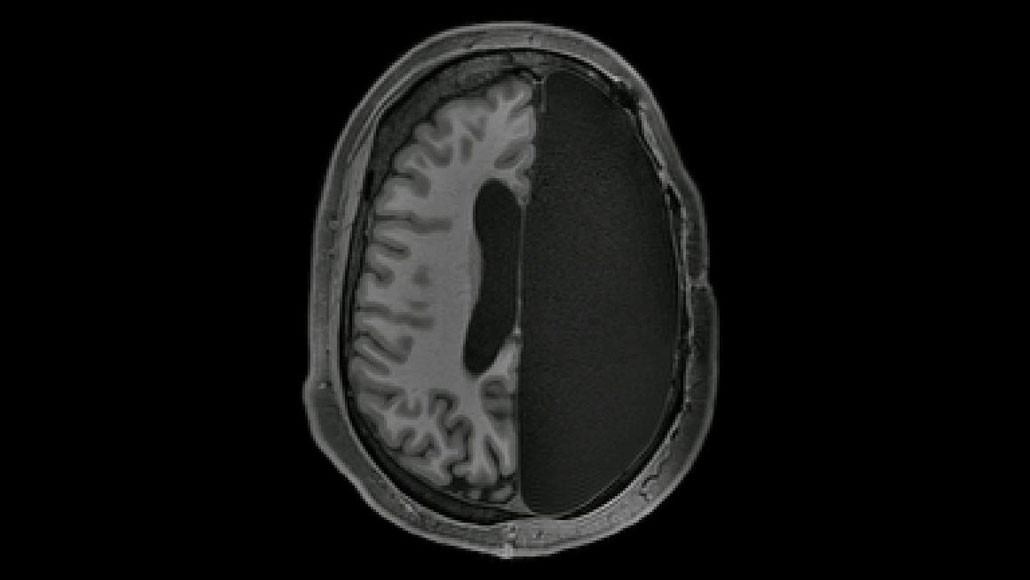

Some people with half a brain have extra strong neural connections

A new study shows how the brain adapts after a hemispherectomy to treat childhood epilepsy

Despite having only half of a brain, certain neural connections appear to be stronger than those in a fully intact brain, a new study suggests.

Half of a brain can do a full-time job.